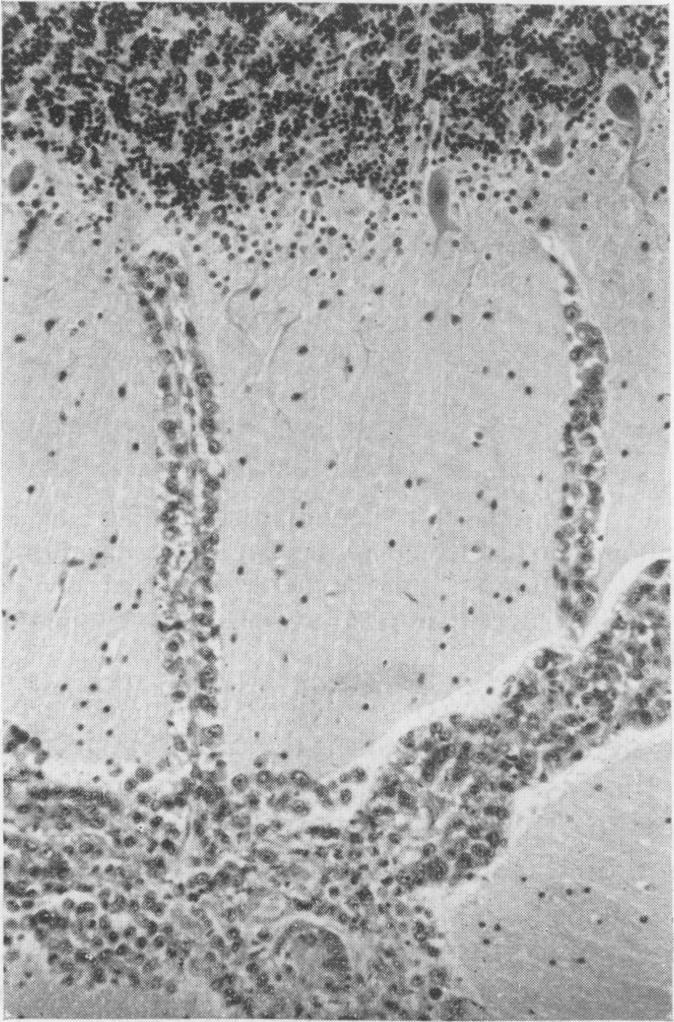

The clinical and pathological features of 63 cases of post-mortem-proved diffuse infiltration of the leptomeninges by tumour are presented. A wide variety of tumours of the nervous system, both primary and secondary, was found to give rise to such involvement, with adenocarcinoma having a particular propensity to behave in this manner. Dysfunction of cranial and spinal nerves, a confusional state and headache were prominent clinical features. Examination of the cerebro-spinal fluid was found to be less useful diagnostically in cases of primary tumours of the nervous system with leptomeningeal involvement than in cases of diffuse infiltration of the meninges by carcinoma.